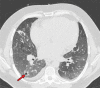

Chest CT has a potential role in the diagnosis, detection of complications, and prognostication of coronavirus disease 2019 (COVID-19). Implementation of appropriate precautionary safety measures, chest CT protocol optimization, and a standardized reporting system based on the pulmonary findings in this disease will enhance the clinical utility of chest CT. However, chest CT examinations may lead to both false-negative and false-positive results. Furthermore, the added value of chest CT in diagnostic decision making is dependent on several dynamic variables, most notably available resources (real-time reverse transcription-polymerase chain reaction [RT-PCR] tests, personal protective equipment, CT scanners, hospital and radiology personnel availability, and isolation room capacity) and the prevalence of both COVID-19 and other diseases with overlapping manifestations at chest CT. Chest CT is valuable to detect both alternative diagnoses and complications of COVID-19 (acute respiratory distress syndrome, pulmonary embolism, and heart failure), while its role for prognostication requires further investigation. The authors describe imaging and managing care of patients with COVID-19, with topics including (a) chest CT protocol, (b) chest CT findings of COVID-19 and its complications, (c) the diagnostic accuracy of chest CT and its role in diagnostic decision making and prognostication, and (d) reporting and communicating chest CT findings. The authors also review other specific topics, including the pathophysiology and clinical manifestations of COVID-19, the World Health Organization case definition, the value of performing RT-PCR tests, and the radiology department and personnel impact related to performing chest CT in COVID-19. ©RSNA, 2020.